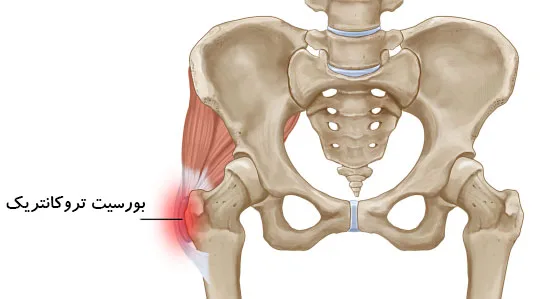

بورسیت لگن، شرایط رایجی است که بخش بیرونی کنار لگن و ران را در بالا تحت تاثیر قرار میدهد اما میتواند همچنین در ناحیه کشاله ران نیز احساس شود. بورسیت لگن، با التهاب بورس که یک کیسه ژله مانند قرار گرفته در لگن و همچنین در کل بدن است، ایجاد میشود.

این آسیب در بین دوندهها رایج است چون بر اثر استفاده بیش از حد و فشار تکراری ایجاد میشود. بورسها ماند ضربهگیر عمل میکنند تا اصطکاک بین استخوان و بافت نرم را کاهش دهند اما وقتی تحریک شده و ملتهب میشوند، باعث درد در آن نواحی خواهند شد.

دو نوع بورس بزرگ در لگن وجود دارد که بیشتر مستعد بورسیت هستند. دوندهها معمولاً در بخش بیرونی استخوان لگن (تروکانتر بزرگ) درد را احساس میکنند و التهاب این بورس، بورسیت تروکانتریک نامیده میشود.

بورسیت کمتر رایج، التهاب بورس تهیگاهی مازویی قرار گرفته داخل لگن (بخش کناری کشاله ران) است. اگرچه این شرایطی در مقایسه با بورسیت تروکانتریک، کمتر رایج است، اما به همان شیوه درمان میشود.